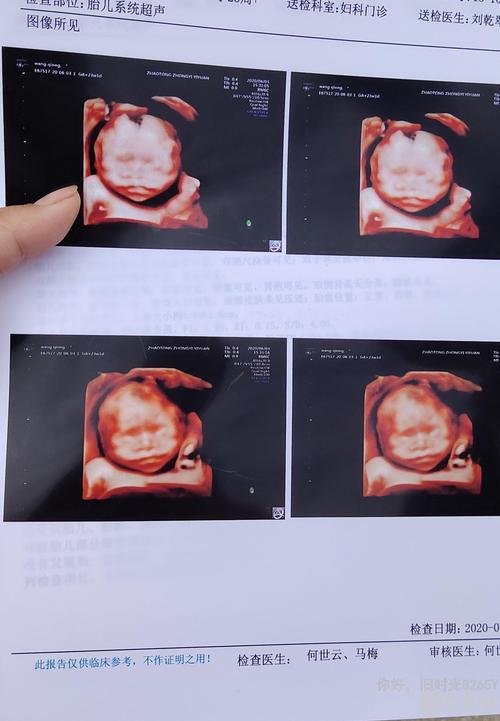

四维兔唇图片,轻度兔唇四维彩超图片

轻度兔唇四维彩超图片

四维彩超兔唇照片

四维彩超轻微兔唇图片

四维兔唇图片是什么样

四维彩超图片

四维图片

胎儿四维照片

宝宝四维照片